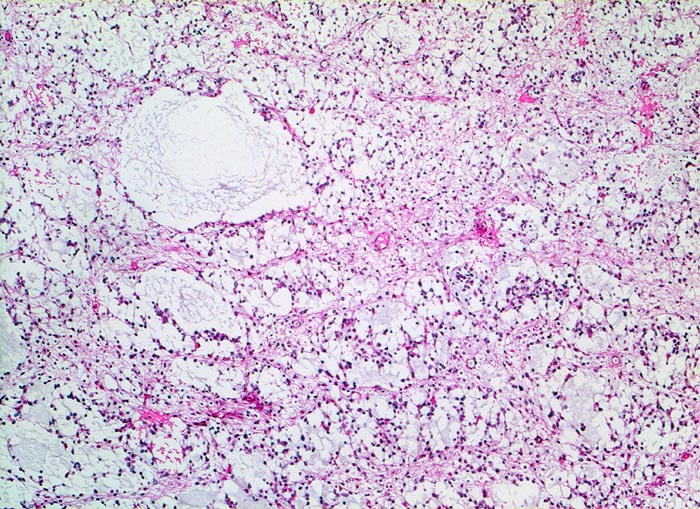

PathoPic ID 5256 - Oligodendrogliom (WHO Grad II)

Oligodendrogliom (WHO Grad II)

maligner Tumor

Hirn frontal

Nervensystem

Fokale mukoide/zystische Degeneration innerhalb des Tumors mit Ausbildung von

Pseudozysten.

Kopfschmerzen und epileptische Anfälle seit zwei Jahren.

Histologie

50